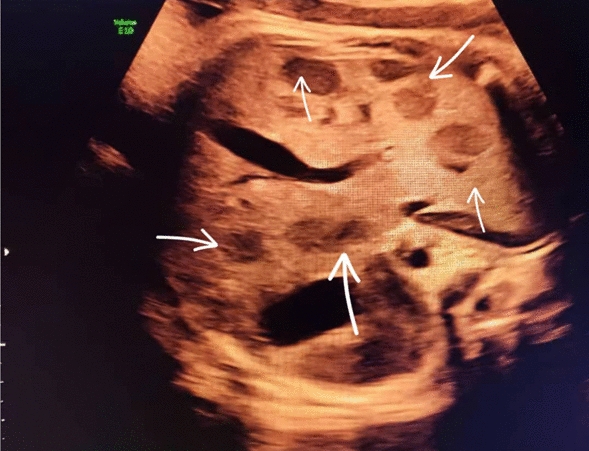

At 37 weeks of gestation, a routine third-trimester ultrasound revealed a hypoechoic lesions in the fetal liver. The lesions were well-circumscribed, measuring approximately 3.5 cm in diameter, and exhibited characteristics suggestive of a vascular tumor. Doppler imaging indicated hypervascularity, raising suspicion for a hemangioendothelioma. Furthermore, the fetal brain appeared normal upon prenatal evaluation. Amniotic fluid levels and fetal growth parameters were within normal limits, and no signs of fetal hydrops were observed. Amniotic fluid levels and fetal growth parameters were within normal limits, and no signs of fetal hydrops were observed. The fetal echocardiogram was normal. Figures 1, 2, and 3

Transverse view of the fetal abdomen obtained by sonography shows multiple hypoechoic lesions, indicated by arrows